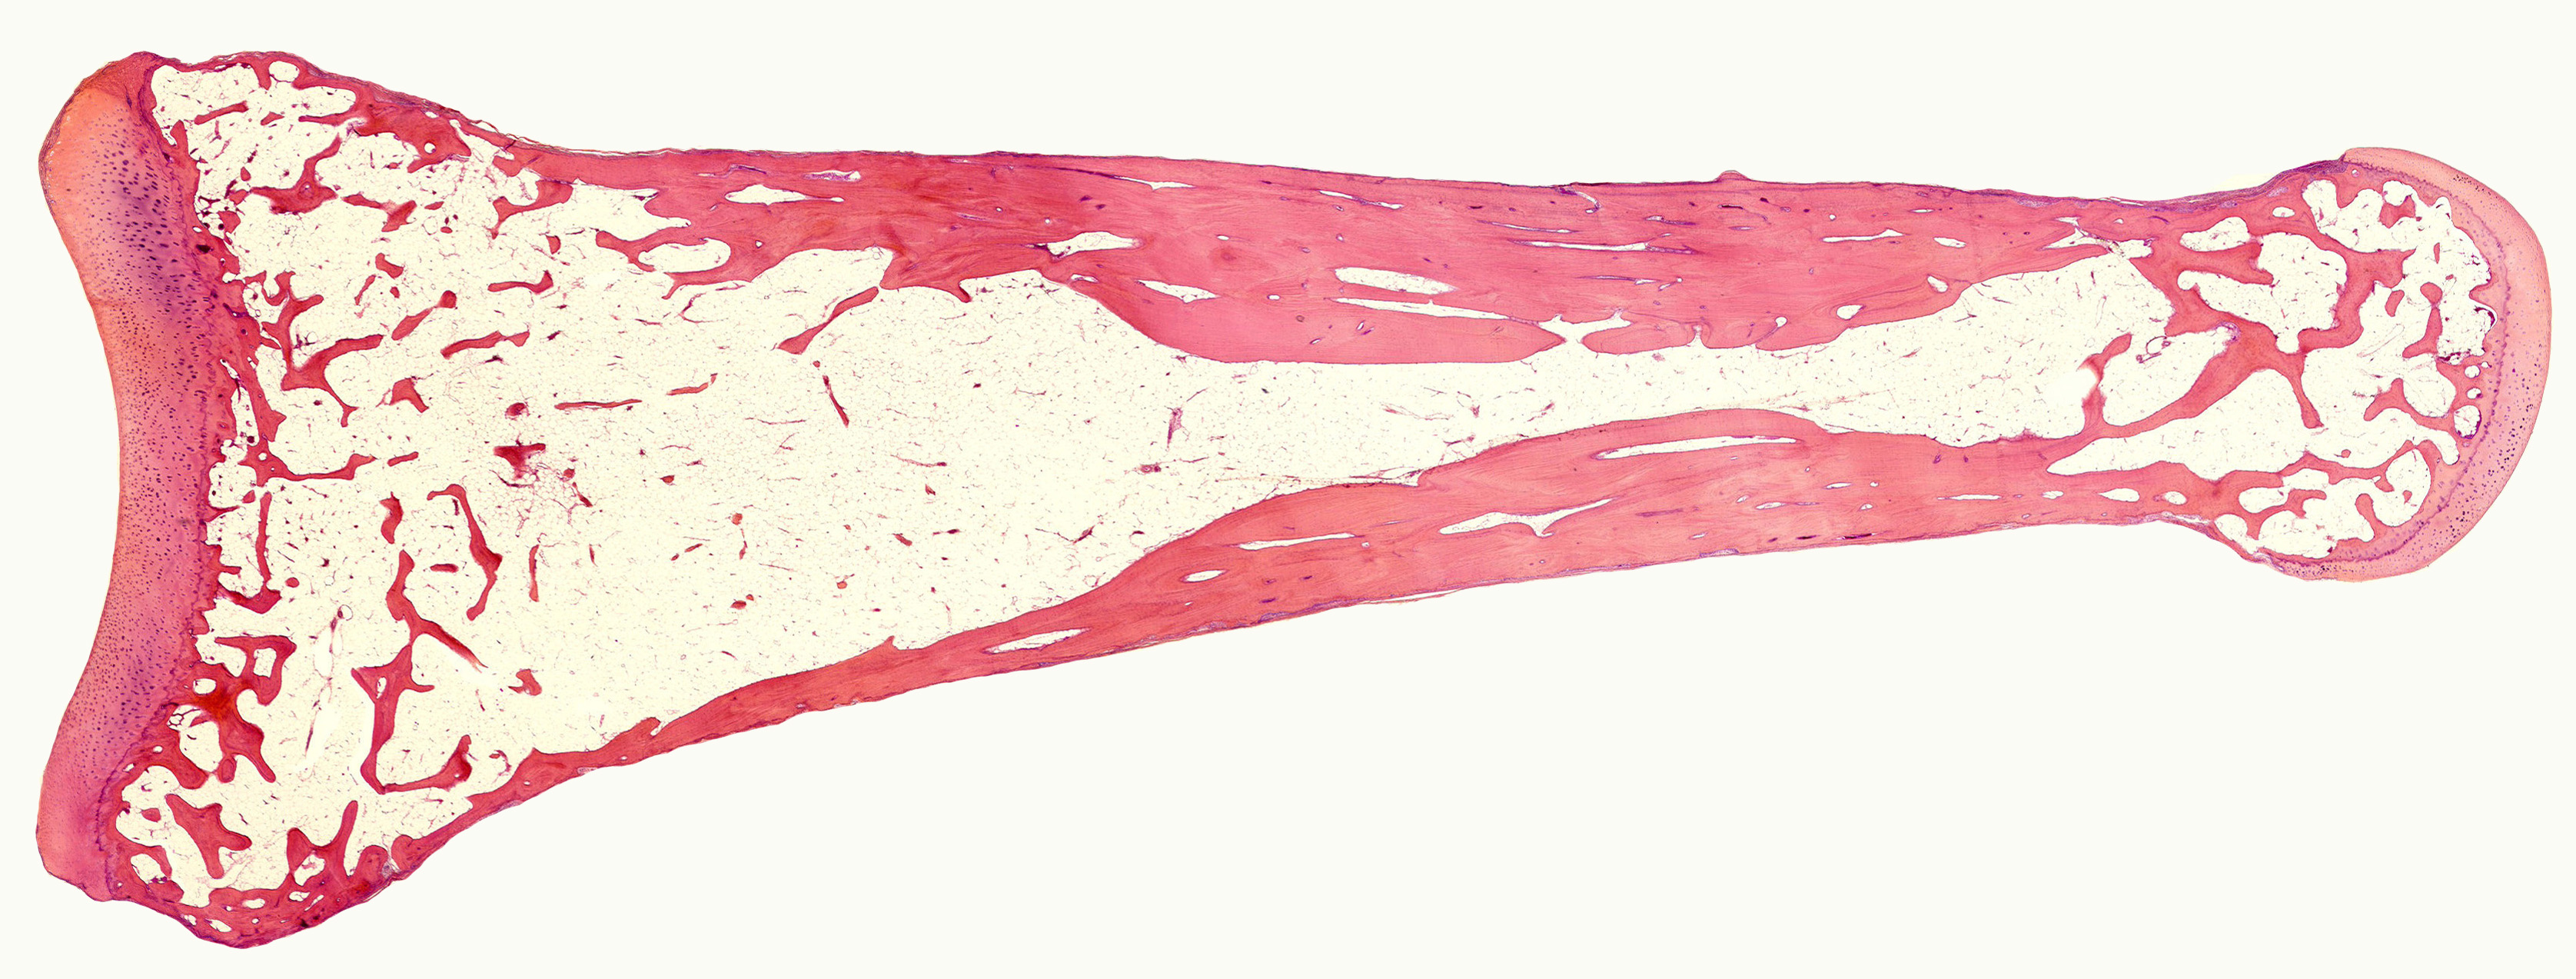

slide 40A finger bone vlp 2

Published December 9, 2015 at 3351 × 1273 in Welcome

Human phalanx (t.arnett@ucl.ac.uk)